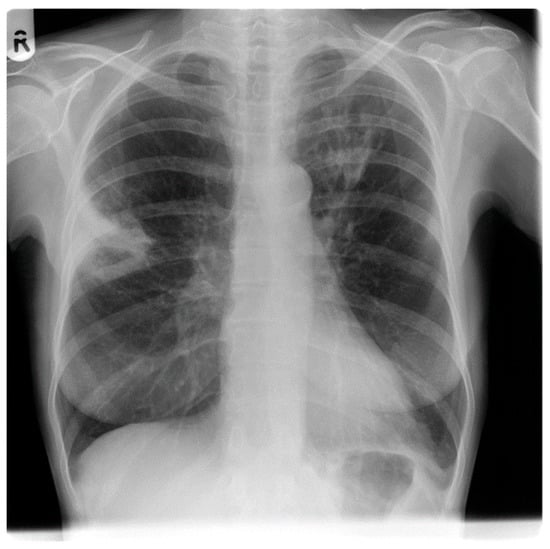

1.6.4. Radiology